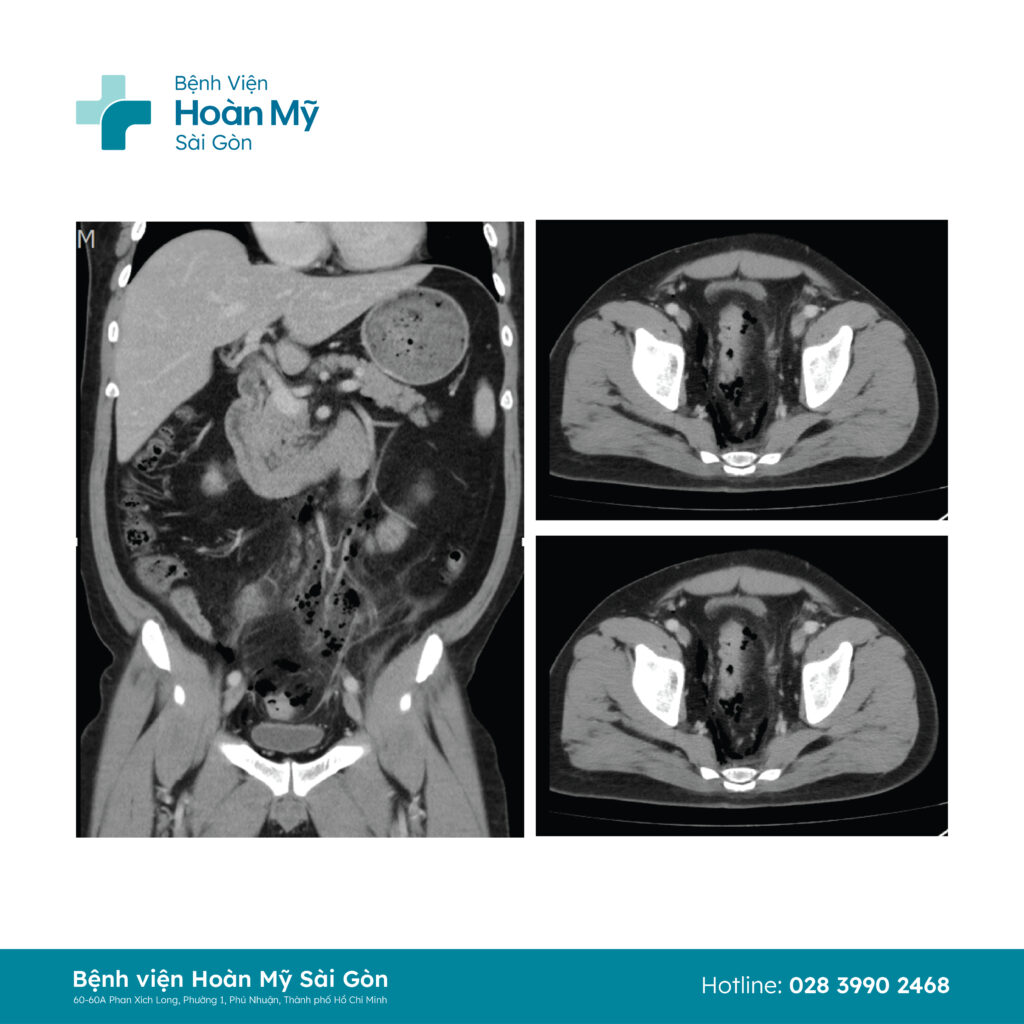

Kết quả cho thấy anh T. bị đa túi thừa đại tràng chậu hông, trực tràng kèm thâm nhiễm mô mỡ, dịch xung quanh, đặc biệt là khí tự do kéo dài dọc mạc treo đại trực tràng, lan xa đến hạ vị. Anh được chẩn đoán viêm túi thừa đại tràng chậu hông giai đoạn WSES 2B (túi thừa viêm thủng, khí tự do di chuyển xa trong ổ bụng), ngay lập tức anh T. được chỉ định phẫu thuật cấp cứu, nội soi ổ bụng, rửa bụng, cắt đoạn ruột chứa túi thừa viêm thủng và nối ruột một thì.

Ảnh chụp cắt lớp vi tính cho thấy túi thừa đại tràng thâm nhiễm mỡ xung quanh